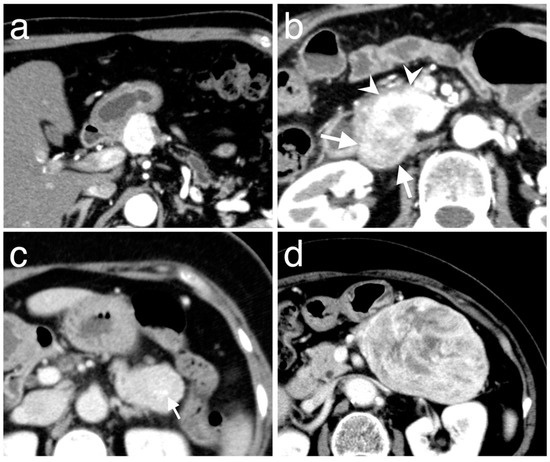

3.3. Enhancement Patterns of Pan-NENs Related to Low or High PAX6 Expression

| Hyperenhancement | 4 | 32 | 0.64 | 0.009 |

| Iso- or hypoenhancement b | 7 (3, 4) | 8 (6, 2) | ||

| Portal phase | ||||

| Hyperenhancement | 3 | 33 | 0.76 | 0.001 |

| Iso- or hypoenhancement b | 8 (6, 2) | 7 (6, 1) | ||